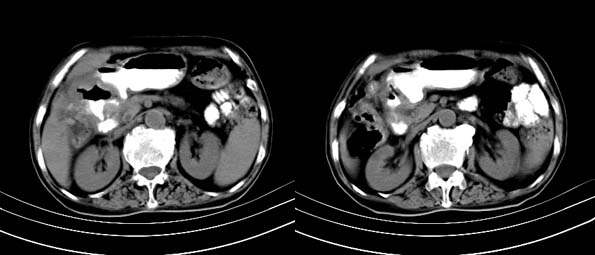

以下是引用bailaode在2008-6-12 22:10:00的发言:[br]资料中未提及患者有无急腹症体征,这个很重要。[br] ct表现:肝内境界模糊之低密度灶,内有含对比剂之液气平面.(提示肝内病灶与胃肠道沟通) [br] 1、根据“长城干红 ”所提供的资料“患者,女,74岁,黑便月余,消瘦,一般状况差,白细胞1万四千”,是否可认为是个慢性病程?那么我首先考虑:十二指肠结核,十二指肠--胆管瘘,继发胆道逆行感染肝脓肿形成。[br] 2、如有急腹症体征则考虑:十二指肠溃疡穿孔?十二指肠占位伴穿孔?

以下是引用拾荒者在2008-6-13 22:13:00的发言:[br]病灶与升结肠、肝脏及十二指肠关系密切,且结肠降段见造影剂影,支持结肠与十二指肠瘘形成,原因及原发病在哪不好定,不过,虽说有风险,但还是应该手术治疗,单纯抗感染估计不行。